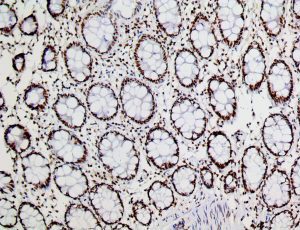

The first cytokines released are interleukin 1β (IL-1β) and tumor necrosis factor-α (TNF-α), which attract a variety of circulating white blood cells (WBCs) to the infection site, including neutrophils, monocytes, macrophages, and natural killer (NK) cells. This response, along with the antipathogenic chemicals released by these cells (i.e., complement), comprise the innate immune response. These cells directly attack the invading pathogen and also release additional cytokines, chief among them interleukin-1 and 6 (IL-6). IL-6 is essential for invoking the adaptive immune response, which calls T-cells, B-cells, and T helper (Th) cells to the infection site. IL-6 also stimulates further recruitment, proliferation and activation of macrophages.

This activation induces inflammatory monocytes to highly express IL-6, starting a localized and then systemic cascade effect that results in hyperproduction of IL-6, which accelerates the inflammatory process. Because IL-6 also increases vascular permeability, excessive levels cause blood vessels to become very leaky. This, along with clotting factors released from vascular endothelial cells, stimulates the coagulation cascade, resulting in microthrombosis (tiny clots), which leads to ischemia and tissue death of the kidney, intestines, heart, liver, brain and extremities.